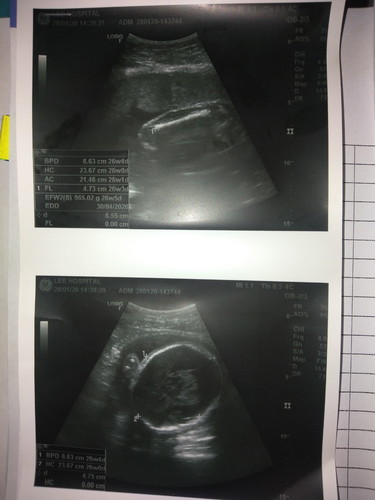

วันนี้ไปอัลตร้าซาวด์มาค่ะแล้วภาพขึ้นแบบนี้แต่ว่าตัวเด็กอยู่ตรงไหนคะเขาดูกันยังไงคะ26+4

หมอให้มาแค่ภาพหัว กับกะดูกแขนหรือขานี่แหละค่ะแม่

เปนหัวกับกระดูกขาค่ะ